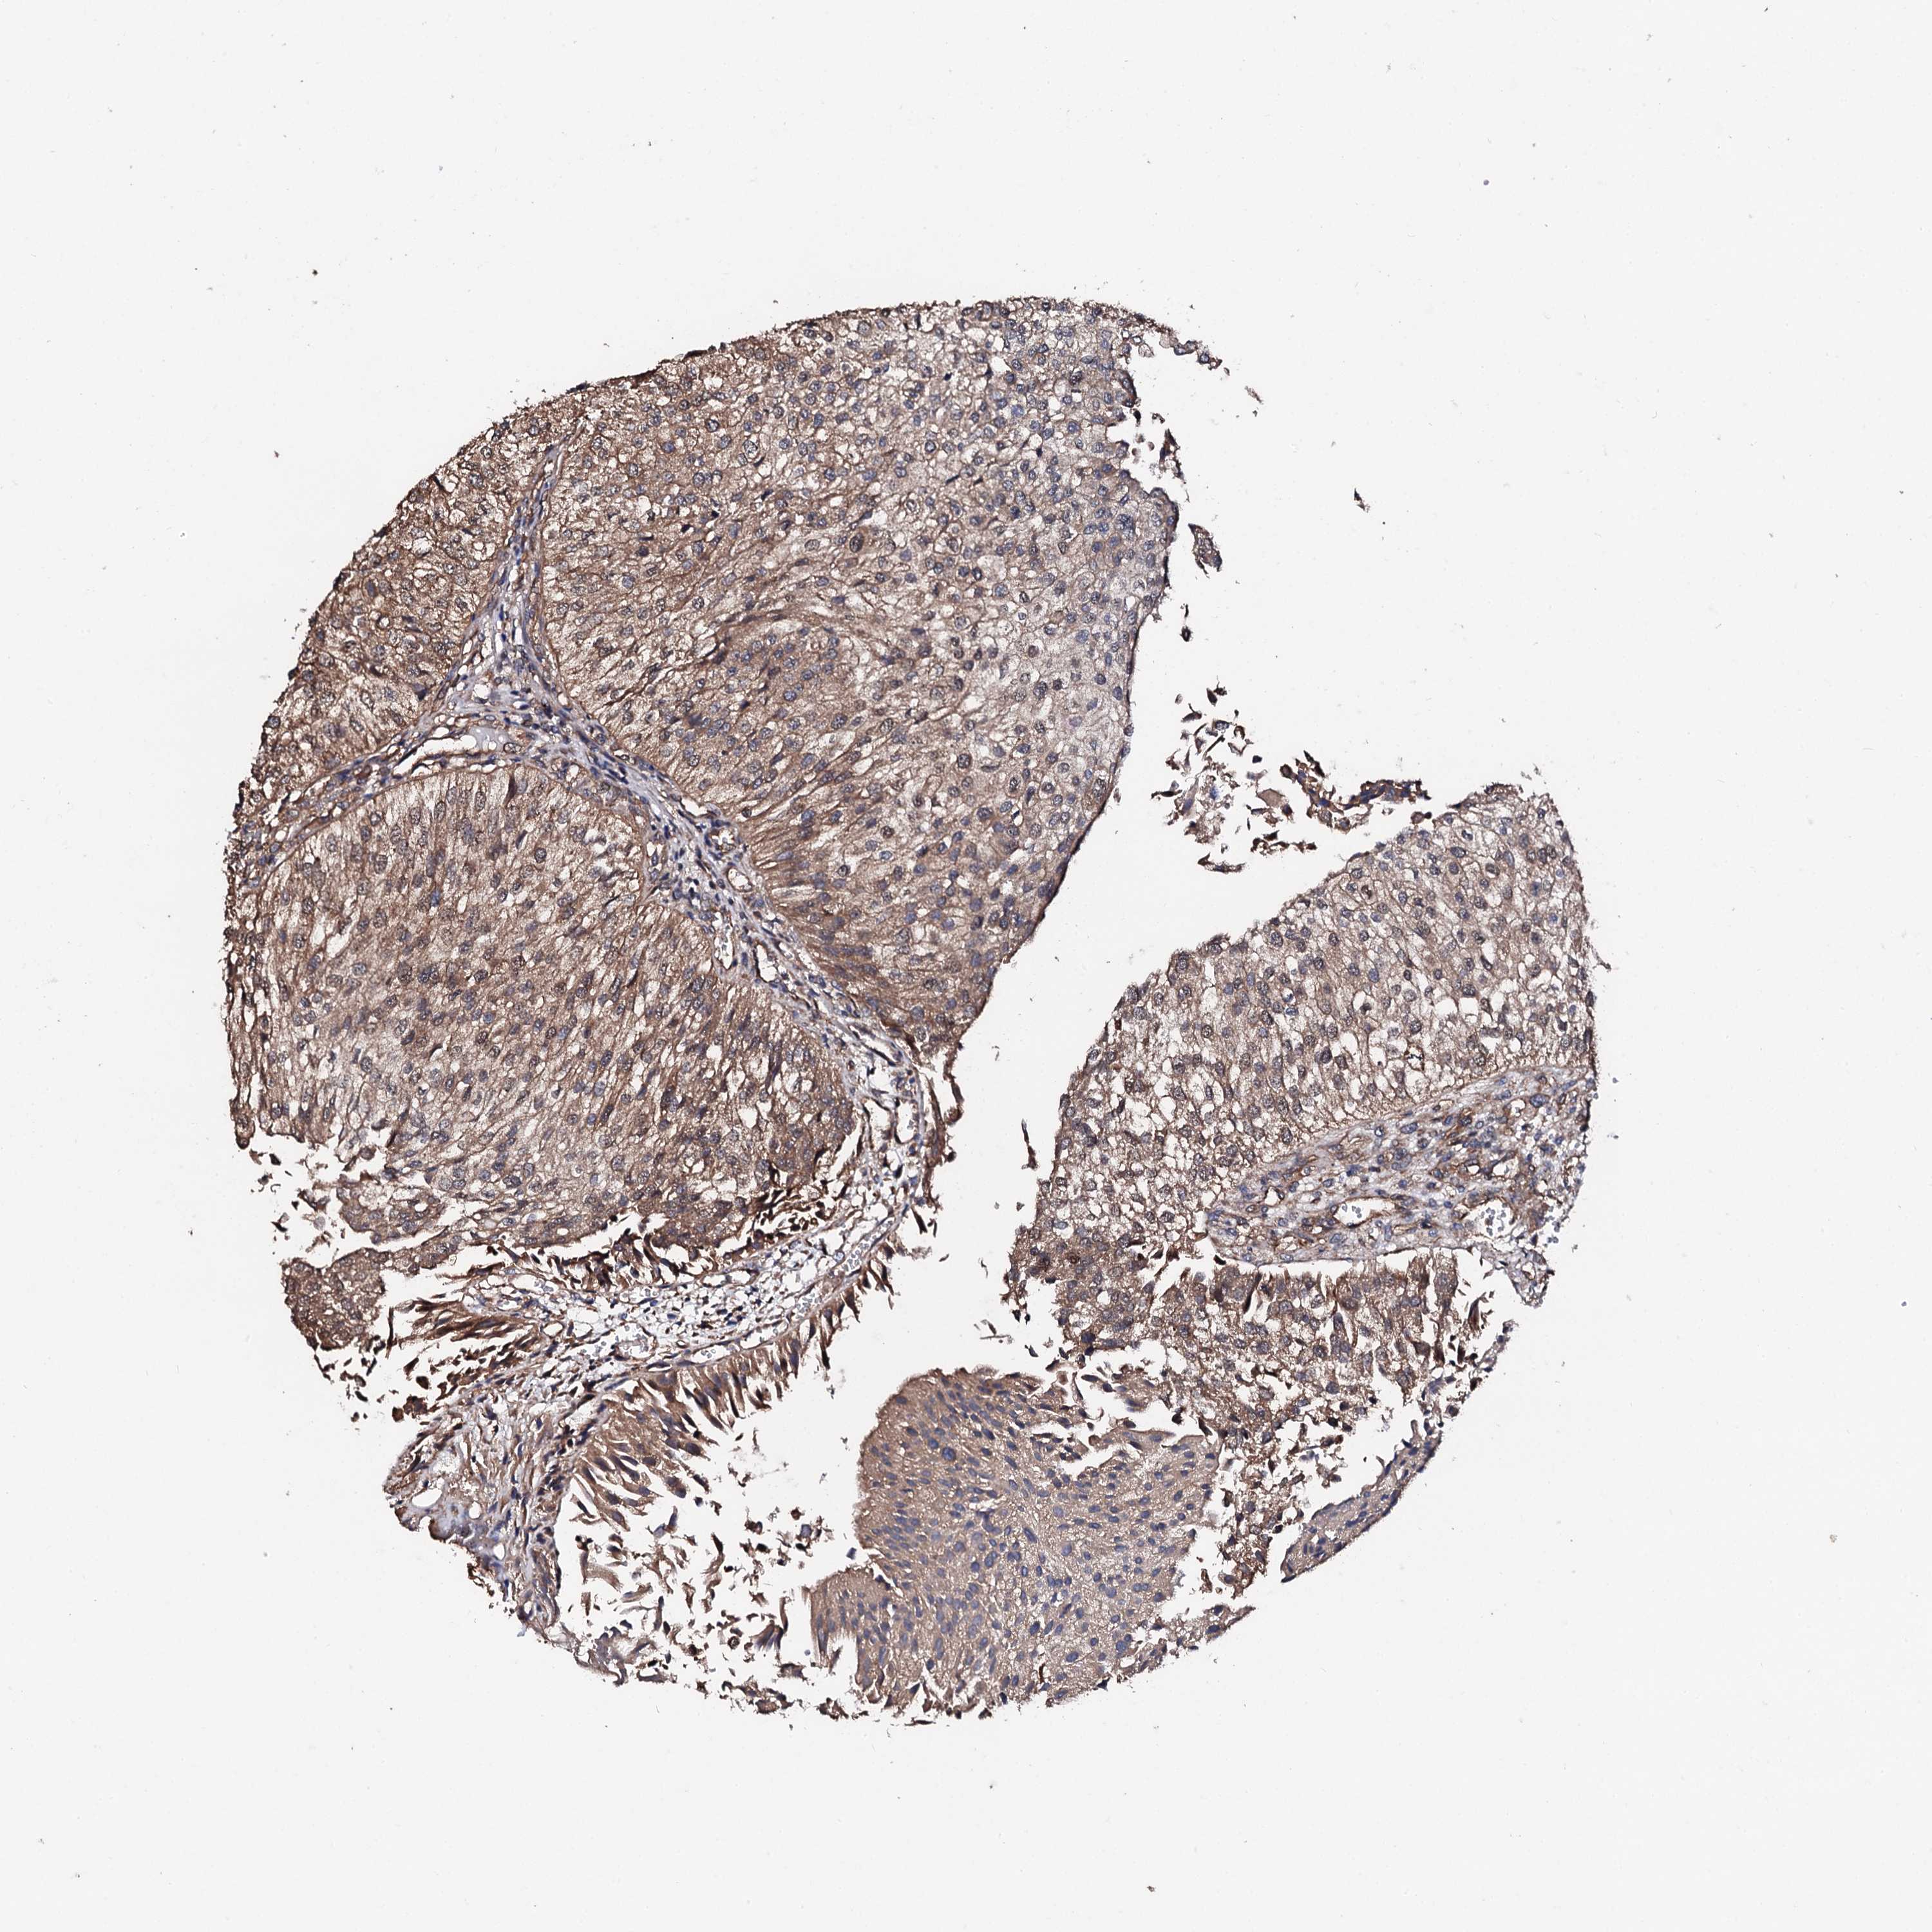

UROTHELIAL CANCER - Protein expressioni

A mouse-over function shows sample information and annotation data. Click on an image to view it in a full screen mode. Samples can be filtered based on level of antibody staining by selecting one or several of the following categories: high, medium, low and not detected. The assay and annotation is described here.

Note that samples used for immunohistochemistry by the Human Protein Atlas do not correspond to samples in the TCGA dataset.

Antibody stainingi

Antibody staining in the annotated cell types in the current human tissue is reported as not detected, low, medium, or high, based on conventional immunohistochemistry profiling in selected tissues. This score is based on the combination of the staining intensity and fraction of stained cells.

Each image is clickable and will lead to virtual microscopy that enables deeper exploration of all samples and also displays staining intensity scores, fraction scores and subcellular localization as well as patient and tissue information for each sample.

Antibody HPA039377

Antibody HPA040375

Urothelial carcinoma, High grade

Urothelial carcinoma, Low grade